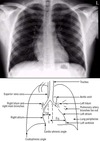

On a Posterior-Anterior CXR, the normal right heart and mediastinal border are made up of four structures. Name them from the bottom to the top.

* Inferior Vena Cava (bottom) * Right Atrium * Ascending Aorta * Superior Vena Cava (top)

On a Posterior-Anterior CXR, the normal left heart and mediastinal border comprise five structures. Name them from the bottom to the top.

* Left Ventricle (bottom) * Left Atrium * Pulmonary Artery * Aortic Arch * Subclavian Artery/Vein (top)

Label 1

* Aortic Arch

57

Label 2

* Pulmonary Trunk

58

Label 3

* Left atrial appendage

59

Label 4

* Left Ventricle

60

Label 5

* Right Ventricle

61

Label 6

* Superior Vena Cava

62

Label 7

* Right hemidiaphragm

63

Label 8

* Left hemidiaphragm

64

Label 9

* Horizontal fissure

65

* Oblique Fissure

66

67

* Thoracic spine/ Retrocardial space

68

* Retrosternal space